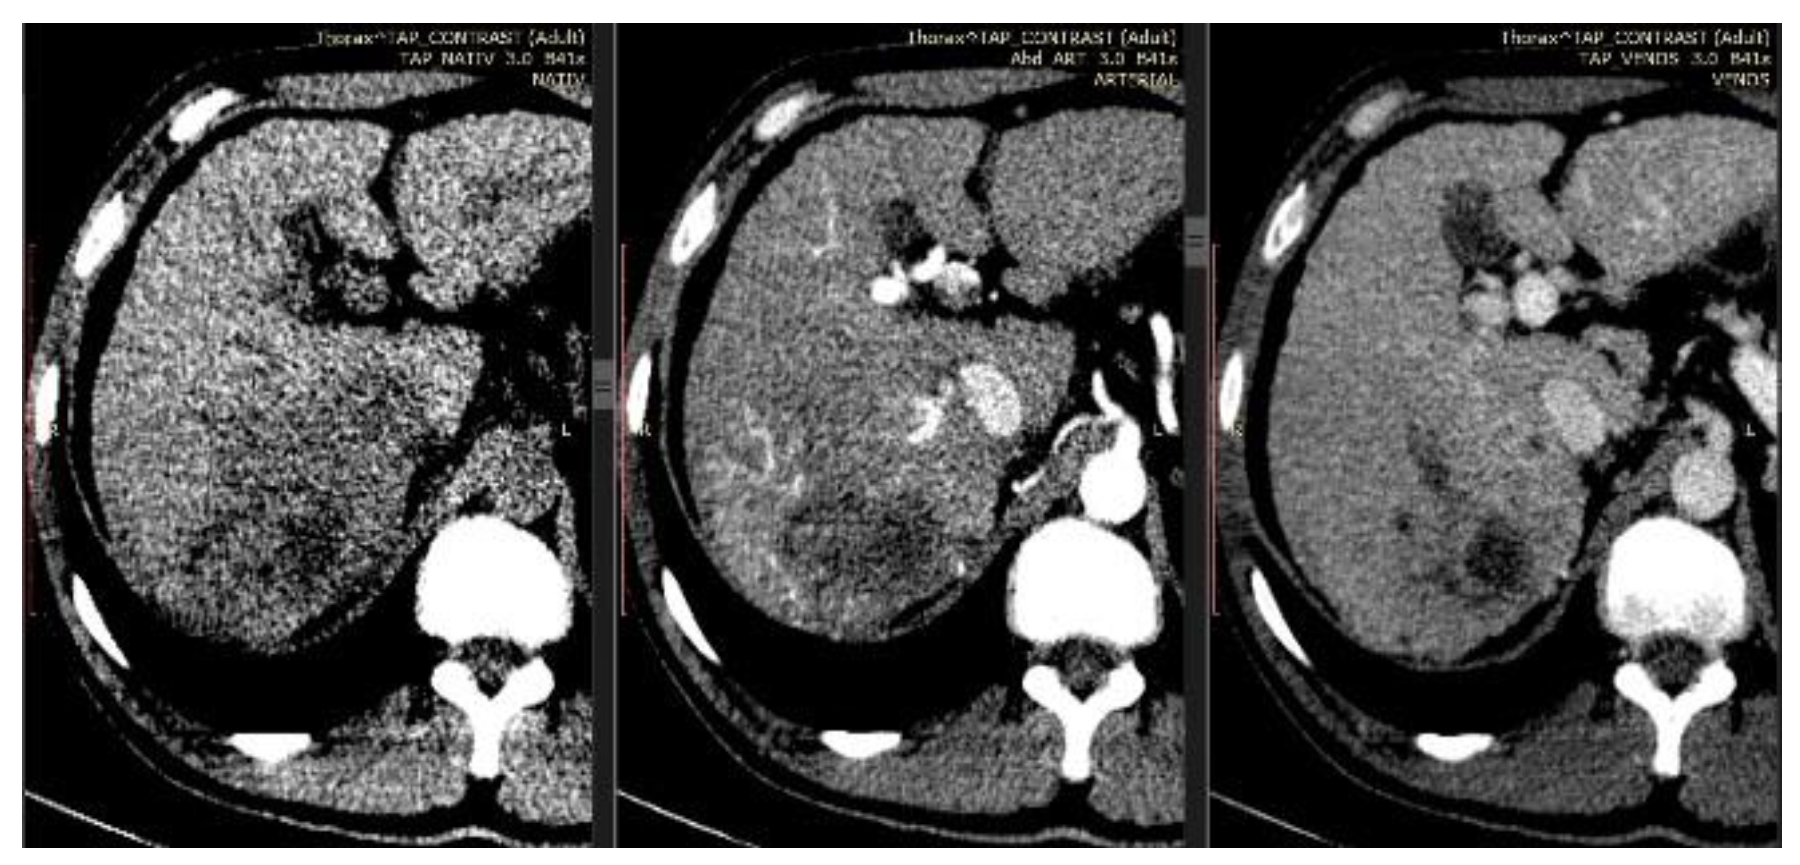

Case report